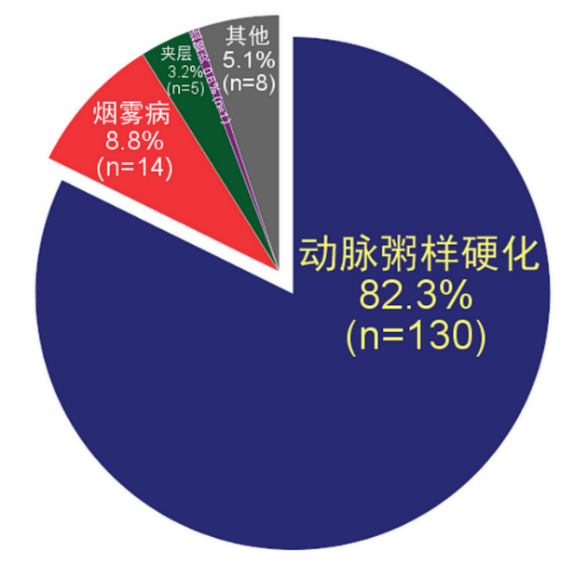

3、症状性颅内动脉狭窄病因研究

通过应用优化的T1-VISTA(西门子称为SPACE)序列对症状性颅内动脉狭窄患者的颅内动脉管壁进行成像研究发现,在158例患者中,导致颅内动脉狭窄的病因依次为动脉粥样硬化(82.3%)、烟雾病(8.8%)、动脉夹层(3.2%)、血管炎(0.6%)及其他原因不明疾病(5.1%)(图4)。本研究还发现动脉粥样硬化患者的低密度脂蛋白(2.8±1.1 mmol/L vs. 2.3±0.6 mmol/L, p = 0.022)和总胆固醇(4.4±1.4 mmol/L vs. 3.6±1.3 mmol/L, p = 0.019)水平显著高于非动脉粥样硬化患者。图5为颅内动脉粥样硬化、烟雾病、动脉夹层和血管炎患者的磁共振管壁特征。该研究结果提示,颅内动脉粥样硬化是导致国人症状性颅内动脉狭窄的最主要原因,其他非动脉粥样硬化疾病依次为烟雾病、夹层、血管炎和原因不明疾病。与非动脉粥样硬化性疾病相比,动脉粥样硬化患者表现为较高的低密度脂蛋白和总胆固醇水平。

图4 颅内动脉狭窄病因分布